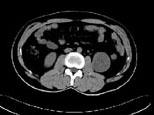

问题 女,63岁,左腰部隐痛不适1个月余,CT平扫+增强如图所示,下列哪项诊断正确 ( )

选项 A、左肾下极脓肿 B、左肾下极淋巴瘤 C、左肾下极错构瘤 D、左肾下极癌 E、左肾下极囊肿

答案 D